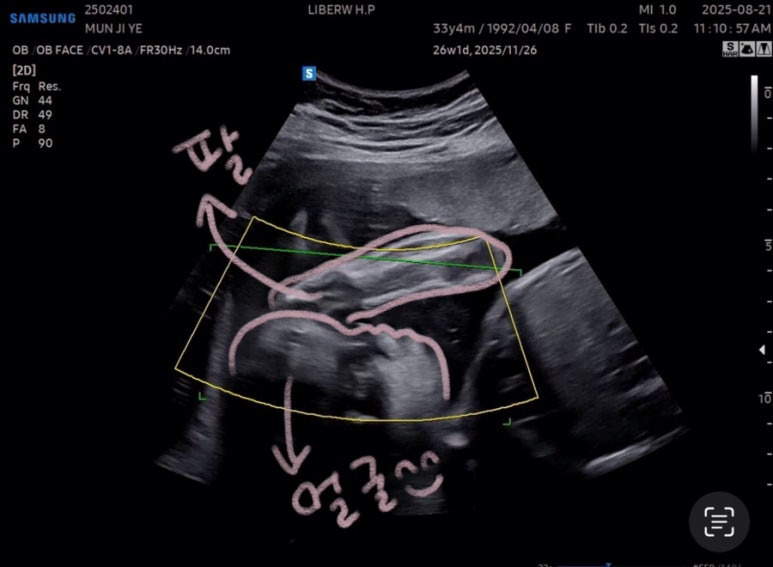

아쉽게도

사탕이는 얼굴을 가리고 있었다🥲

안쪽에 팔로 얼굴 가리고 숨은 사탕

이 상태로 찍어봤지만,,,!

여기까지가 최선이었다^^,,,

또르르🥲

사탕아~~ 코만 구경하라는 거니~~~?

잘 안 보여서 다시 찍어볼 겸

사탕이가 왼쪽으로 누우면 잘 움직이길래

옆으로 누운 상태로

선생님이 열심히 흔들어주셨다!

하지만 결과는 그대로 ㅎㅎ